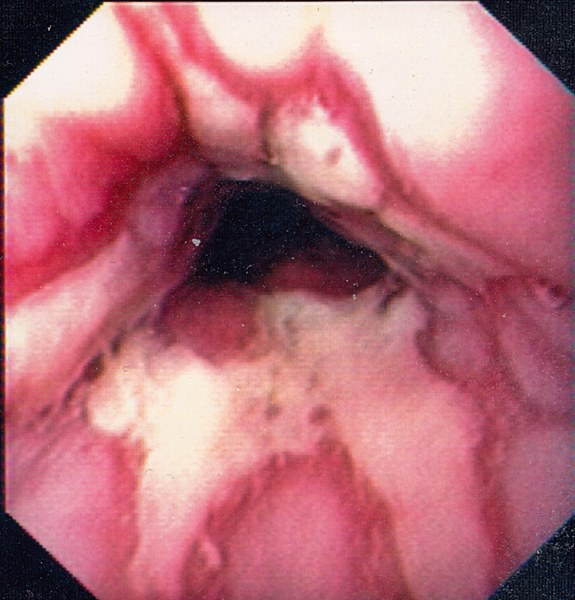

Reflux Oesophagitis Grade D (Los Angeles Classification)